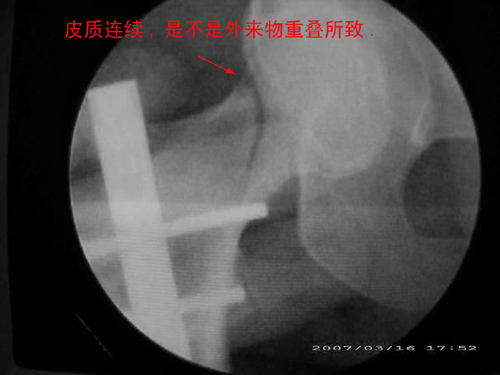

患者,女,因外伤就诊。摄骨盆及右股骨。当时报告骨盆未见明显异常,右股骨中段粉碎性骨折。五天后行股骨中段骨折内固定手术,术中摄床边片示股骨颈骨折。现把术前和术中图像上传。请大家高诊,分析股骨颈骨折是术前漏诊还是其他原因。术前骨盆片右股骨颈显示欠佳是由于股骨中段骨折无法将股骨颈完全显示。

标题: 重叠?

重叠?

回头看术前片,可见一低密透光区.

关于楼主说的骨折线的形态,的确和一般外伤的有种不太一样的感觉,上方裂隙较明显,下方骨皮质“连续”,我认为成年人应该是全部断了的,不全骨折的可能性非常非常小,该片恰好无法全部显示骨折线。骨折线的形态不能判定术前还是术后骨折。以上只是个人小小看法,请各位老师指正为谢!